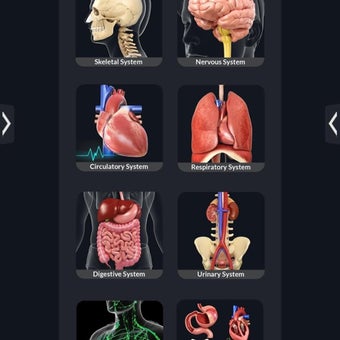

La anatomía humana es una aplicación educativa médica que te permite explorar el cuerpo humano desde todos los ángulos. Ofrece una mirada detallada a la anatomía de los diferentes sistemas, así como a los órganos y sus funciones. Es una referencia perfecta para estudiantes y profesores de medicina.

¿Qué ofrece la aplicación?

Puedes seleccionar cada parte del cuerpo por separado para ver su nombre o leer información relacionada. Puedes ocultar y mostrar cada parte del cuerpo, así como rotar 360° alrededor de un modelo 3D altamente realista. Puedes dibujar en la pantalla o compartir capturas de pantalla con tus amigos. Puedes encontrar la definición de cada parte del cuerpo y su anatomía.